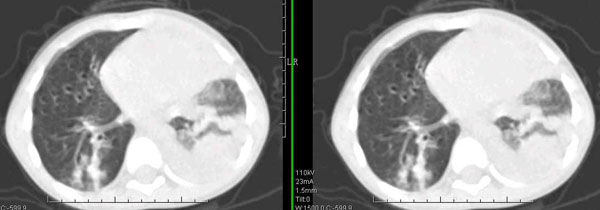

男孩,4岁,发热咳嗽4天。

下面补充ct图片:

此病人是我接手的,发热、咳嗽来做胸透,透视见左侧肺野大部密实,纵隔、心影明显左移,呼吸示纵隔摆动、膈肌矛盾运动(透视下采集了几幅图片),左肺动度明显减弱。询问病人家长,没有吃花生米等呛咳史。由于其影像特征明显,当时诊断:考虑左侧支气管异物并阻塞性肺不张、肺炎。

病人去上级医院支气管镜取出了异物。今天询问上级医院耳鼻喉科主任(是我同学),得知病人异物为胶冻样合并有少许白色粉末,后小儿说晚上喝药片时呛咳过,考虑当时为药片阻塞;另外支气管镜检发现小儿左侧支气管发育略窄,经住院抗炎治疗,现病人基本康复。

多谢各位关注及精彩点评!追踪病人结果时才知道还做过ct检查!对不起!有点晚了,刚刚下载,上传供大家参考!